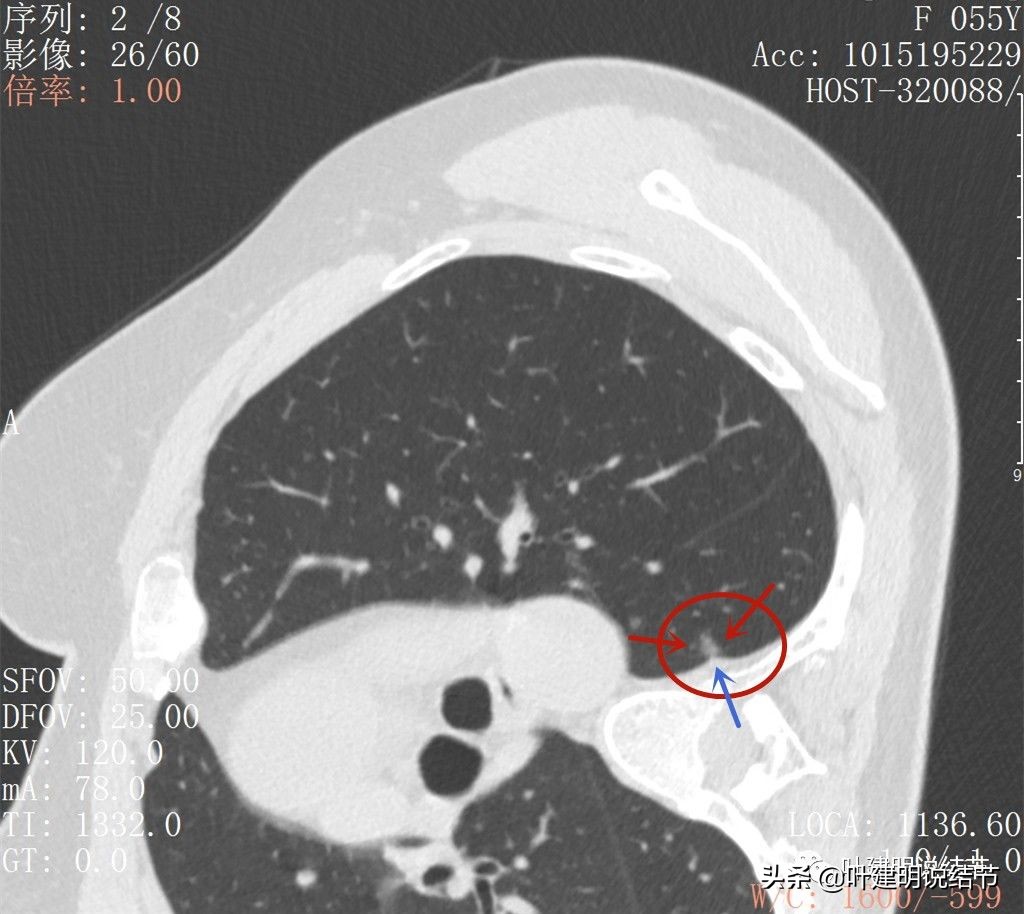

再来看2022年6月的CT图像:

病灶轮廓很清,邻近胸膜是略有影响的(蓝色箭头)